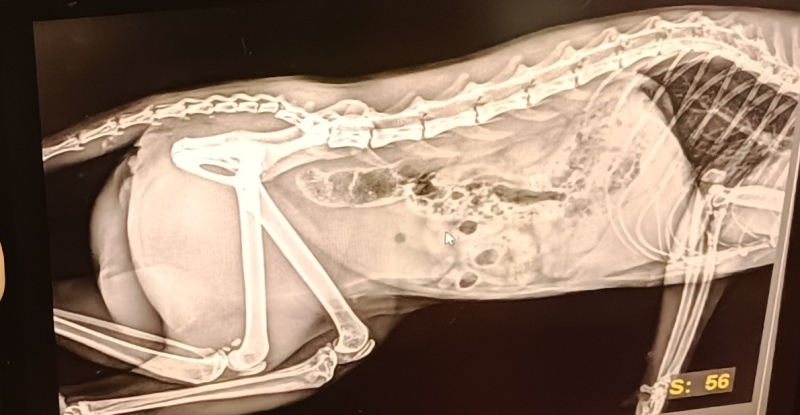

18 listopada odwiedziła nas kuzynka Jasia - lekarz weterynarii z Przychodni dla zwierząt „Veterinarius”. Pani Angelika, opowiedziała dzieciom o pracy weterynarza oraz przekazała wiele cennych informacji dotyczących zdrowia naszych pupili. Wytłumaczyła dzieciom, jak ważne są regularne wizyty kontrolne, szczepienia oraz odpowiednia dieta.

Przedszkolaki mogły z bliska obejrzeć różne akcesoria potrzebne w pracy weterynarza oraz sprawdzić jak działa stetoskop.